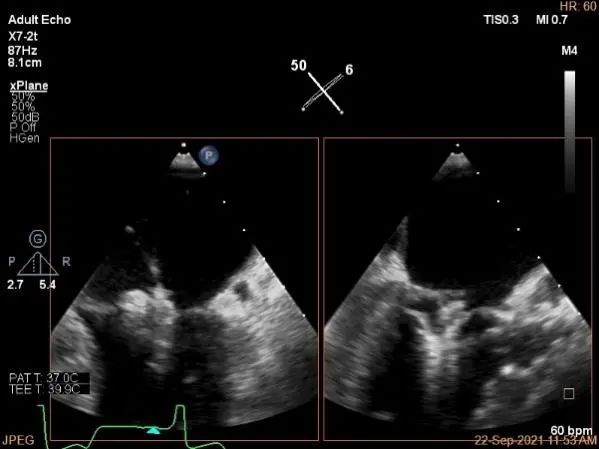

房间隔穿刺点选择

穿刺高度:4.3cm

瓣叶捕获后,前叶抓捕长度9.1mm,后叶抓捕长度7.8mm

外侧残余少量分流

第一个夹子外侧残余小脱垂

残余分流主要来源于残余脱垂区域

评估瓣口条件,平均跨瓣压差:2mmHg,决定在第一个夹子外侧下第二个夹子

第一个夹子外侧放第二个夹子

第二个夹子捕获瓣叶后,前叶抓捕长度9.3mm,后叶抓捕长度7.3mm

未见明确残余分流